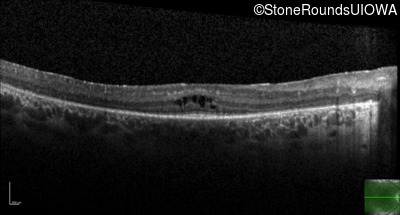

| Age at visit: 25 years |